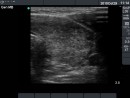

Follow-up examinations (rows from 1st to 8th):

Corresponding sonographic images (row)

2. Note the relation between volume, echogenicity, vascularization and hormone levels.